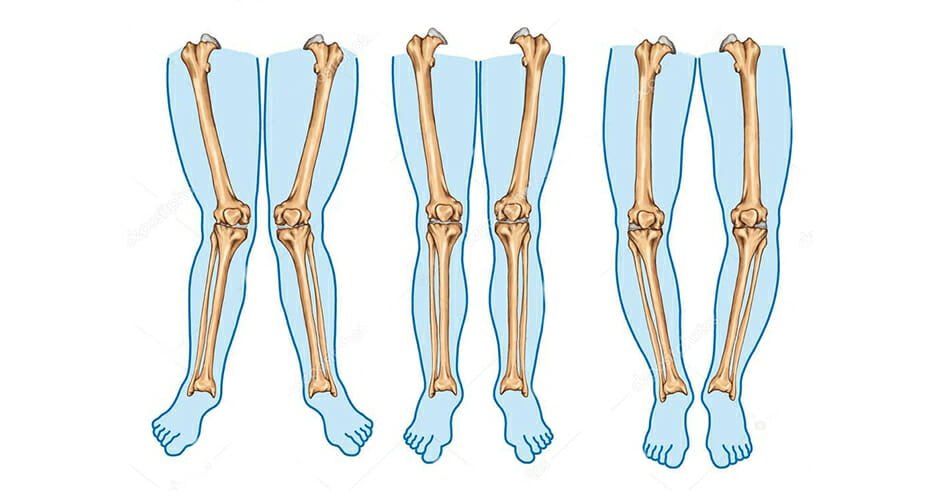

وقتی در حالت عادی میایستیم و قوزکهای پا را در کنار هم قرار میدهیم، نباید فاصله زیادی بین زانوهایمان وجود داشته باشد. همین حالا بایستید؛ اگر به هر دلیلی بین زانوهایتان فاصله غیر طبیعی وجود دارد، بهتر است از همین امروز به فکر درمان و پیشگیری باشید. در این مقاله میخواهیم درباره راههای پیشگیری و درمان پای پرانتزی صحبت کنیم. با ما همراه باشید.

وقتی قوزک پاها را در کنار هم قرار میدهیم، متوجه عدم موازی بودن پاها میشوید. باید بگوییم که حدود ۵ تا ۷ درجه انحراف کاملا طبیعی است. اما اگر این مقدار بیشتر باشد، احتمالا دچار ژنوواروم یا پای پرانتزی شدهاید. از آن جا که زانوی پرانتزی به ساختار اسکلتی پا و زانو بستگی دارد و با افزایش سن و کاهش انعطافپذیری به سختی ترمیم میشود و نیاز به جراحیهای پرهزینه دارد، تشخیص و درمان زودهنگام بهترین عامل موفقیت در درمان است.